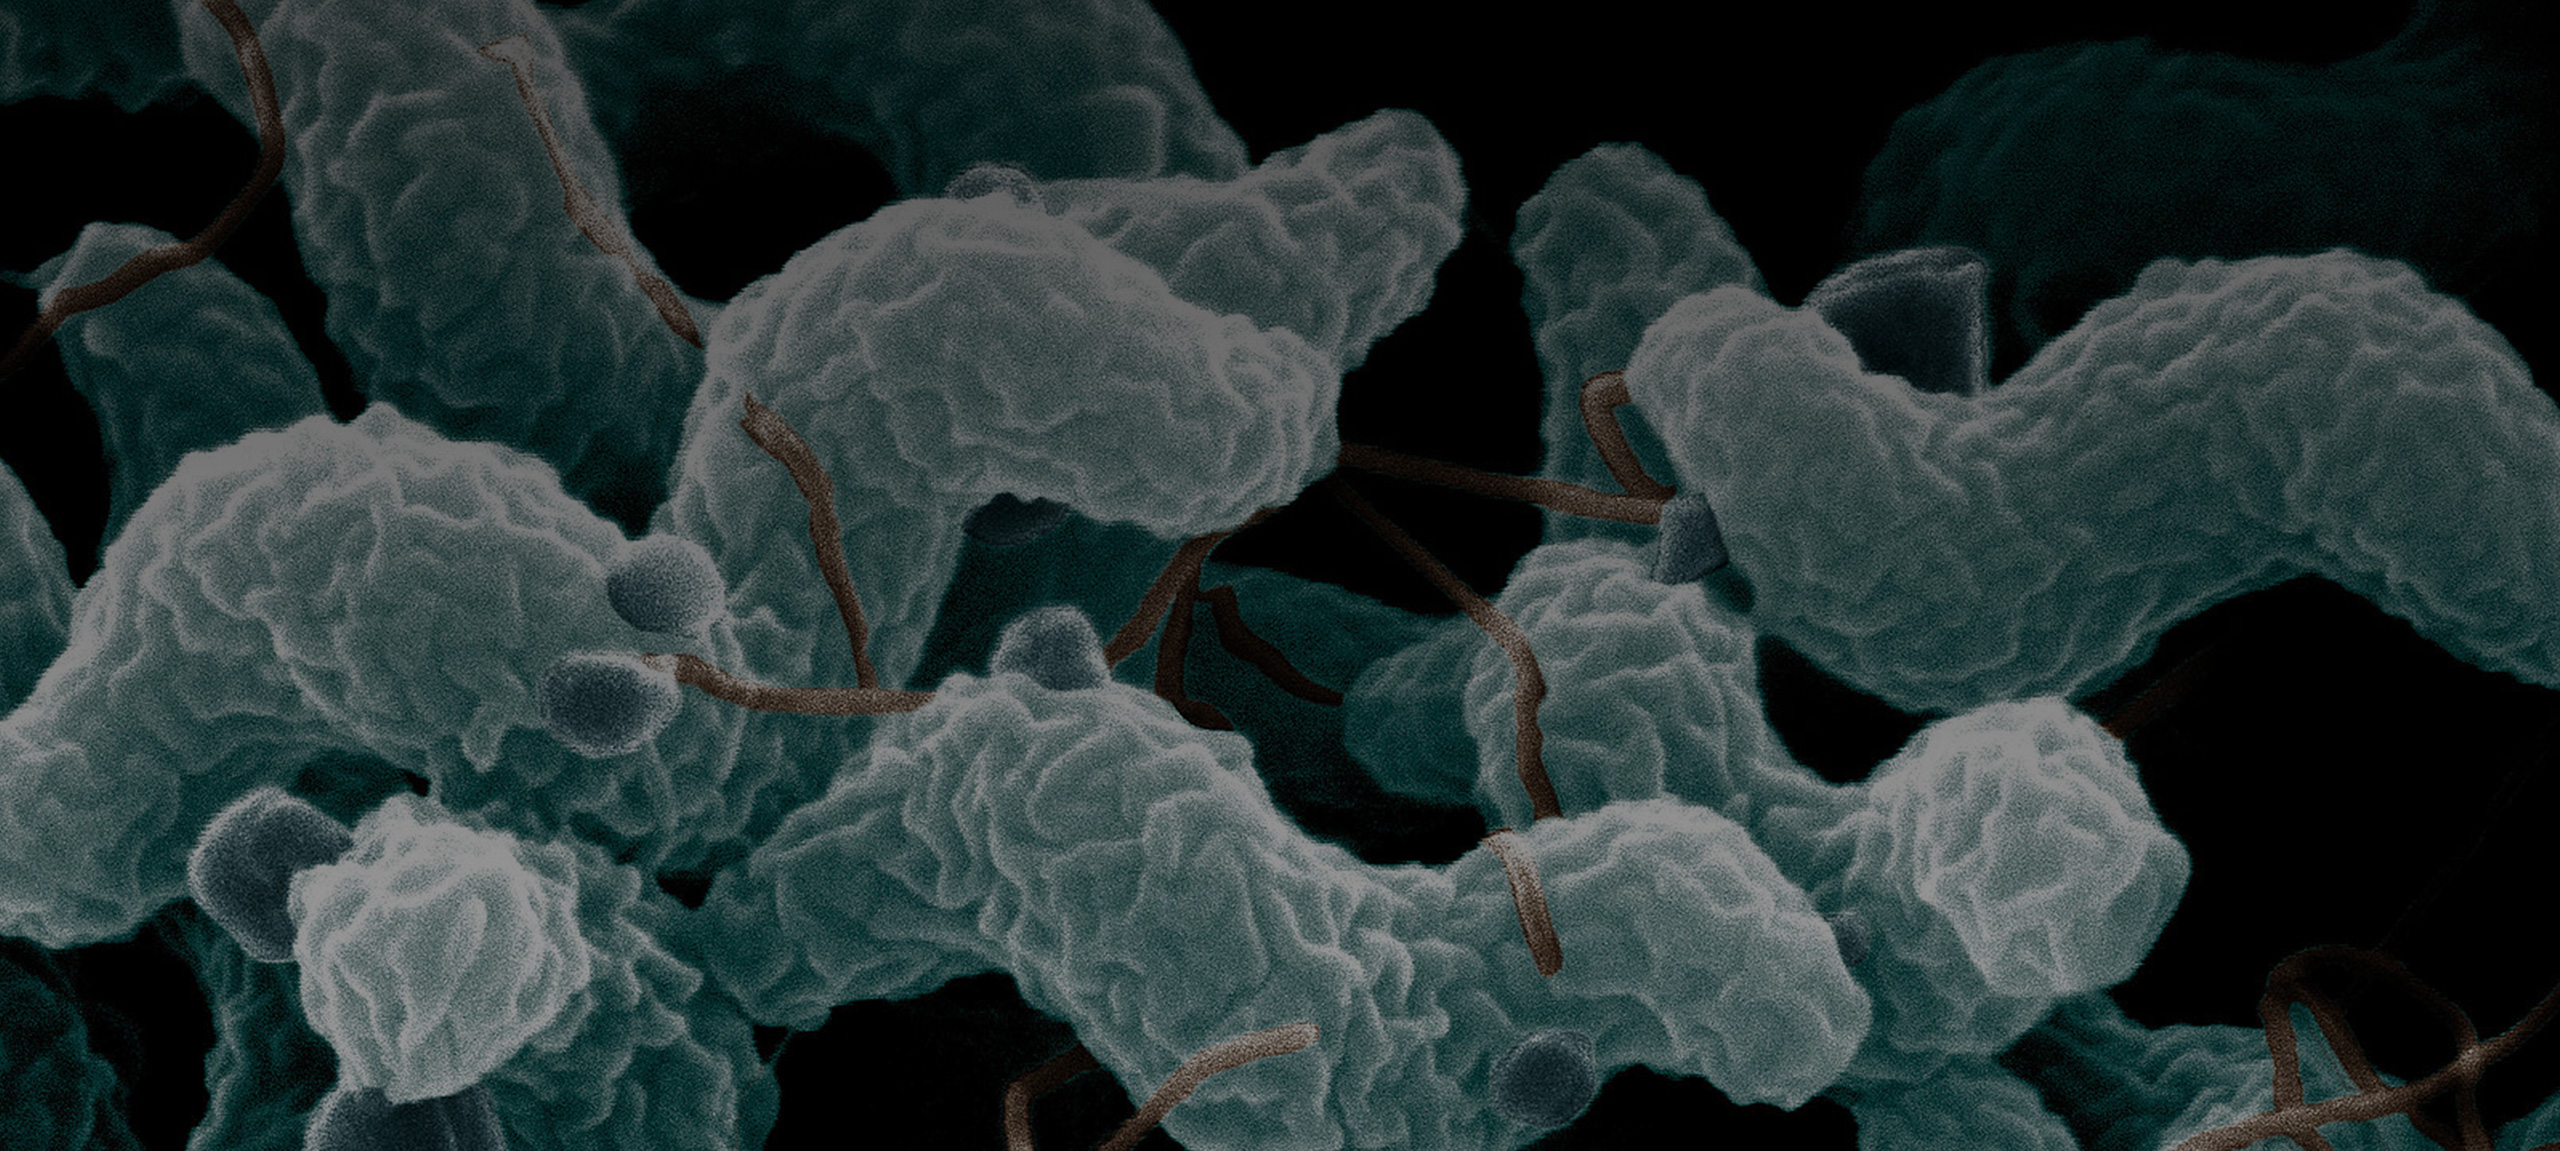

Кампилобактер фетус: патогенез и инфекции

/evrimagaci.org%2Fpublic%2Fcontent_media%2Fb099374a4578fc241a0555a594831216.jpeg)